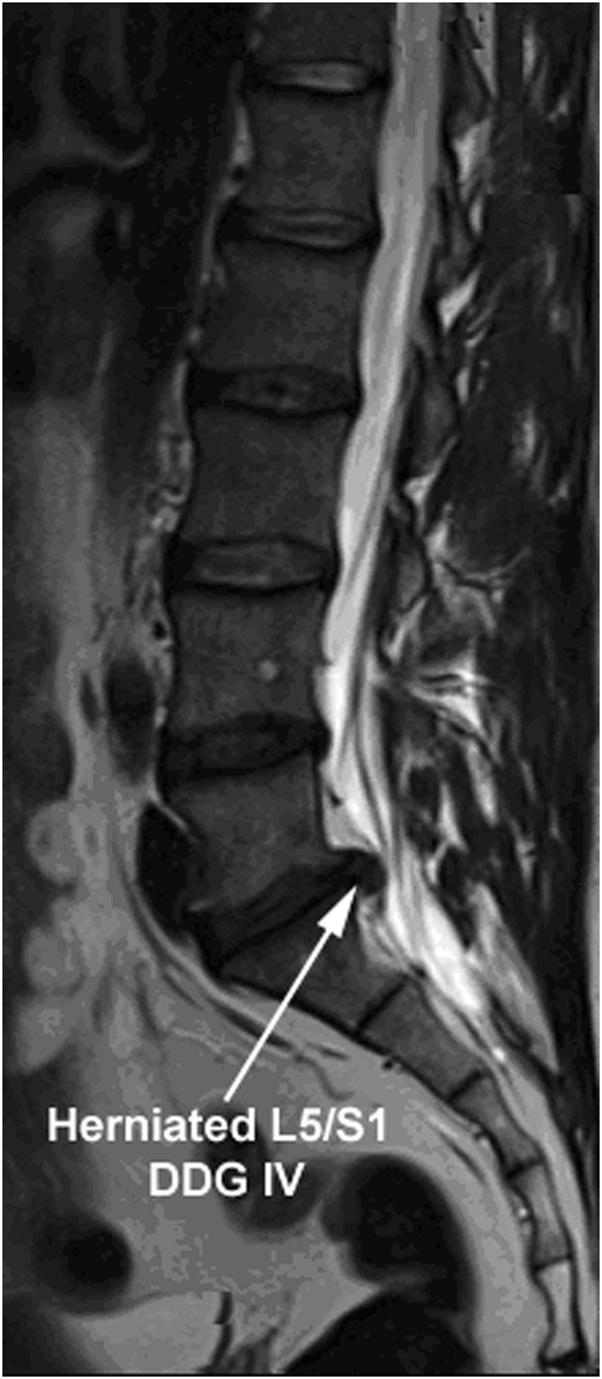

Intervertebral disc (IVD) degeneration damaging the extracellular matrix (ECM) of IVDs is the main cause of spine-associated disorders. Degenerative disc disease (DDD) is a multifaceted disorder, where environmental factors, inflammatory cytokines and catabolic enzymes act together. DDD starts typically due to imbalance between ECM biosynthesis and degradation within IVDs, especially through unbalanced degradation of aggrecan and collagen II in nucleus pulposus (NP). Current treatment approaches are primarily based on conservative or surgical therapies, which are insufficient for biological regeneration. The disintegrins and metalloproteinases with thrombospondin motifs (ADAMTSs) and matrix metalloproteinases (MMPs) are the key proteolytic enzymes for degradation of aggrecan and collagens. Previously, high expression levels of ADAMTS4, ADAMTS5, MMP3 and MMP13, which are accompanied with low levels of aggrecan and collagen II, were demonstrated in degenerative human NP cells. Moreover, self-complementary adeno-associated virus type 6 (scAAV6) mediated inhibitions of ADAMTS4 and ADAMTS5 by RNA-interference (RNAi) could specifically enhance aggrecan level. Thus, MMPs are apparently the main degrading enzymes of collagen II in NP. Furthermore, scAAV6-mediated inhibitions of MMP3 and MMP13 have not yet been investigated. Therefore, we attempted to enhance the level of collagen II in degenerative NP cells by scAAV6-RNAi-mediated inhibitions of MMP3 and MMP13. MRI was used to determine preoperative grading of IVD degeneration in patients. After isolation and culturing of NP cells, cells were transduced with scAAV6-shRNAs targeting MMP3 or MMP13; and analysed by fluorescence microscopy, FACS, MTT assay, RT-qPCR, ELISA and western blotting. scAAV6-shRNRs have no impact on cell viability and proliferation, despite high transduction efficiencies (98.6%) and transduction units (1383 TU/Cell). Combined knockdown of MMP3 (92.8%) and MMP13 (90.9%) resulted in highest enhancement of collagen II (143.2%), whereby treatment effects were significant over 56 days ( < 0.001). Conclusively, scAAV6-RNAi-mediated inhibitions of MMP3 and MMP13 help to progress less immunogenic and enduring biological treatments in DDD.